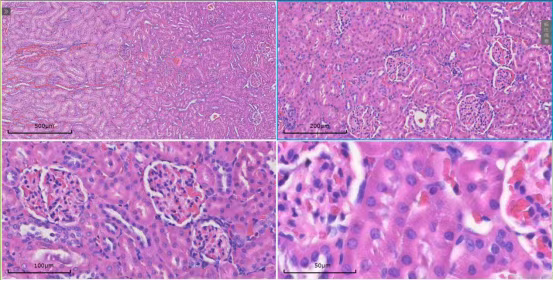

扫描系统覆盖4倍、10倍、20倍及40倍等多个物镜倍数。无论是在4倍镜下观察组织全貌,还是切换至40倍油镜分析细胞亚结构,系统均能确保图像清晰、细节无损,为形态学定量分析提供可靠依据。

针对超大尺寸切片,系统可自动进行图像采集与无缝拼接,生成完整的全景数字切片。研究者可在全景图中快速定位,并直接放大至目标区域进行高倍数观察,实现“整体布局-局部特征”的一体化分析。

该服务专注于提供系统性的扫描方案,尤其适用于心脏、肝脏、脾脏、肺脏及肾脏等主要器官的组织切片。

以肾脏研究为例,该服务还可提供全景扫描与多切面对比的特色解决方案,以满足深度研究需求。

肾全景 横切-纵切